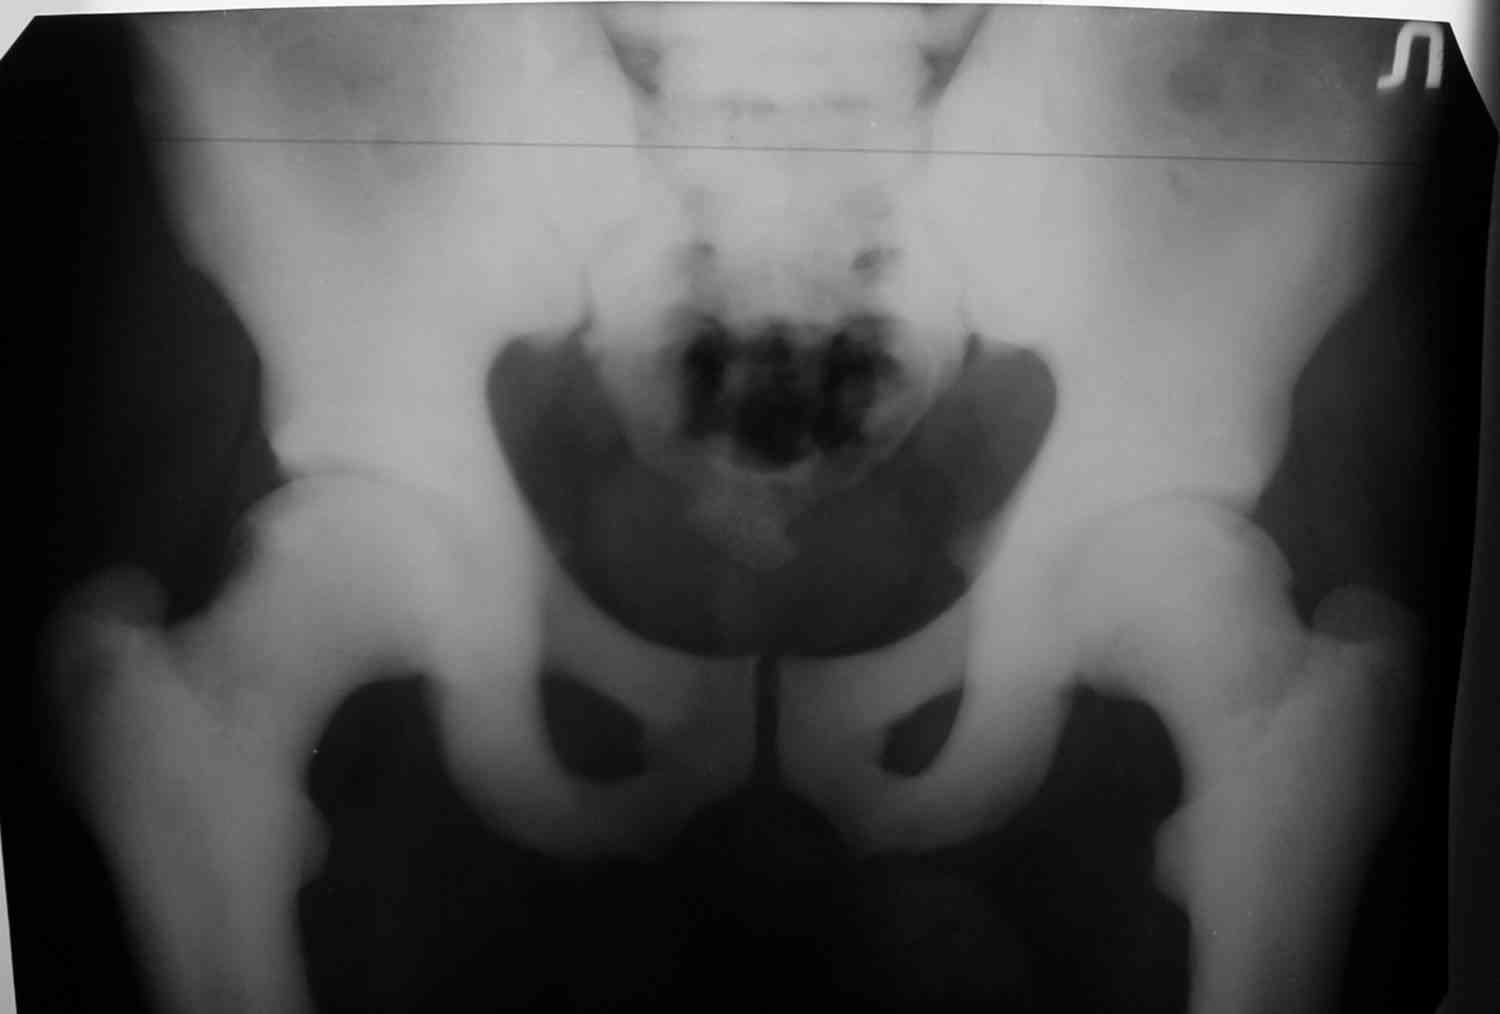

Уважаемый Константин Иванович! Полностью согласен с проф. Михайловым, данный случай не похож на мраморную болезнь, при которой имеется резкое, строго симметричное и генерализованное уплотнение костной ткани (остеопетроз), и кость оказывается построенной преимущественно из гомогенного компактного костного вещества. Для примера привожу случай из архива нашего института (бедренные, плечевые кости и таз, рис 1,2,3)

Изменения структуры костей у Вашего пациента больше похожи на полиоссальную форму фиброзной дисплазии или болезнь Педжета, возможены также инфаркты костного мозга б.берцовых костей. К сожалению, качество снимка не очень хорошее, непонятно, сохранен ли кортикальный слой б.берцовых костей по передней поверхности.

An x-ray pelvis, spine might help in setteling the diagnosis.